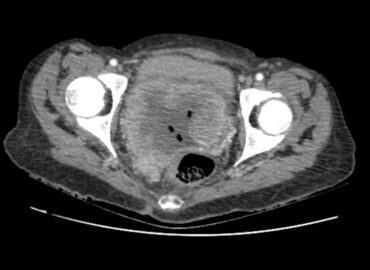

Sexo femenino de 35 años APP Ca de cuello